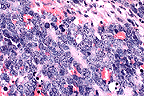

Alveoli filled with characteristic foamy, eosinophilic surfactant and inconspicuous P. carinii organisms in a ferret. (40X, HE, 103K)

P. carinii cyst walls stain well with GMS. (40X, GMS, 103K)

Contributor's Comments: It is felt the corticosteroid treatment rendered the animal susceptible to developing pneumonia. The acute inflammatory reaction is attributed to a bacterial infection, probably coliform and the interstitial pneumonia is attributed to P. carinii. P. carinii cysts were seen with GMS stain.

1. Lung: Pneumonia, interstitial, subacute, multifocal, moderate, with abundant intra-alveolar fungi, Mustela putorius furo, mustelid, etiology consistent with Pneumocystis carinii.

2. 2. Lung: Pneumonia, neutrophilic, diffuse, moderate.

Conference Note: Pneumocystis carinii has a worldwide distribution and inhabits the respiratory tracts of man and many animals. Pneumocystis has caused clinical pneumonia in man, horses, primates, dogs, pigs, goats and other mammals; affected animals and humans are immunosuppressed. Whether P. carinii should be classified as a protozoan or as a fungus has been controversial. However, recent studies of ribosomal RNA, mitochondrial proteins, and genes which encode for thymidylate synthetase suggest that this organism is a fungus.

Pneumocystis carinii possesses two prominent antigens, major surface glycoprotein (MSG), and another 45-55kd molecule of unknown function. Either of these antigens is readily recognized by an immunocompetent host and stimulates both humoral and cell mediated immune responses. In the absence of an immune response however, P. carinii adheres to type I pneumocytes; this attachment may be facilitated by bridging between MSG and fibronectin. Once attached, P. carinii maintains an extracellular, intra-alveolar existence. P. carinii binds surfactant, which is thought to"hide" surface antigens and prevent recognition by the host's immune system. P. carinii pneumonia is suggested by the presence of large amounts of intra-alveolar surfactant, which appears as a foamy, eosinophilic material when stained with hematoxylin and eosin. The organisms stain with methenamine silver, periodic acid- Schiff, and Gram's stain.

Concurrent infections with bacteria, other fungi, or viruses are common in immunocompromised hosts. In this case, coliform bacteria were cultured from the lung and very likely were the cause of the neutrophilic inflammation.